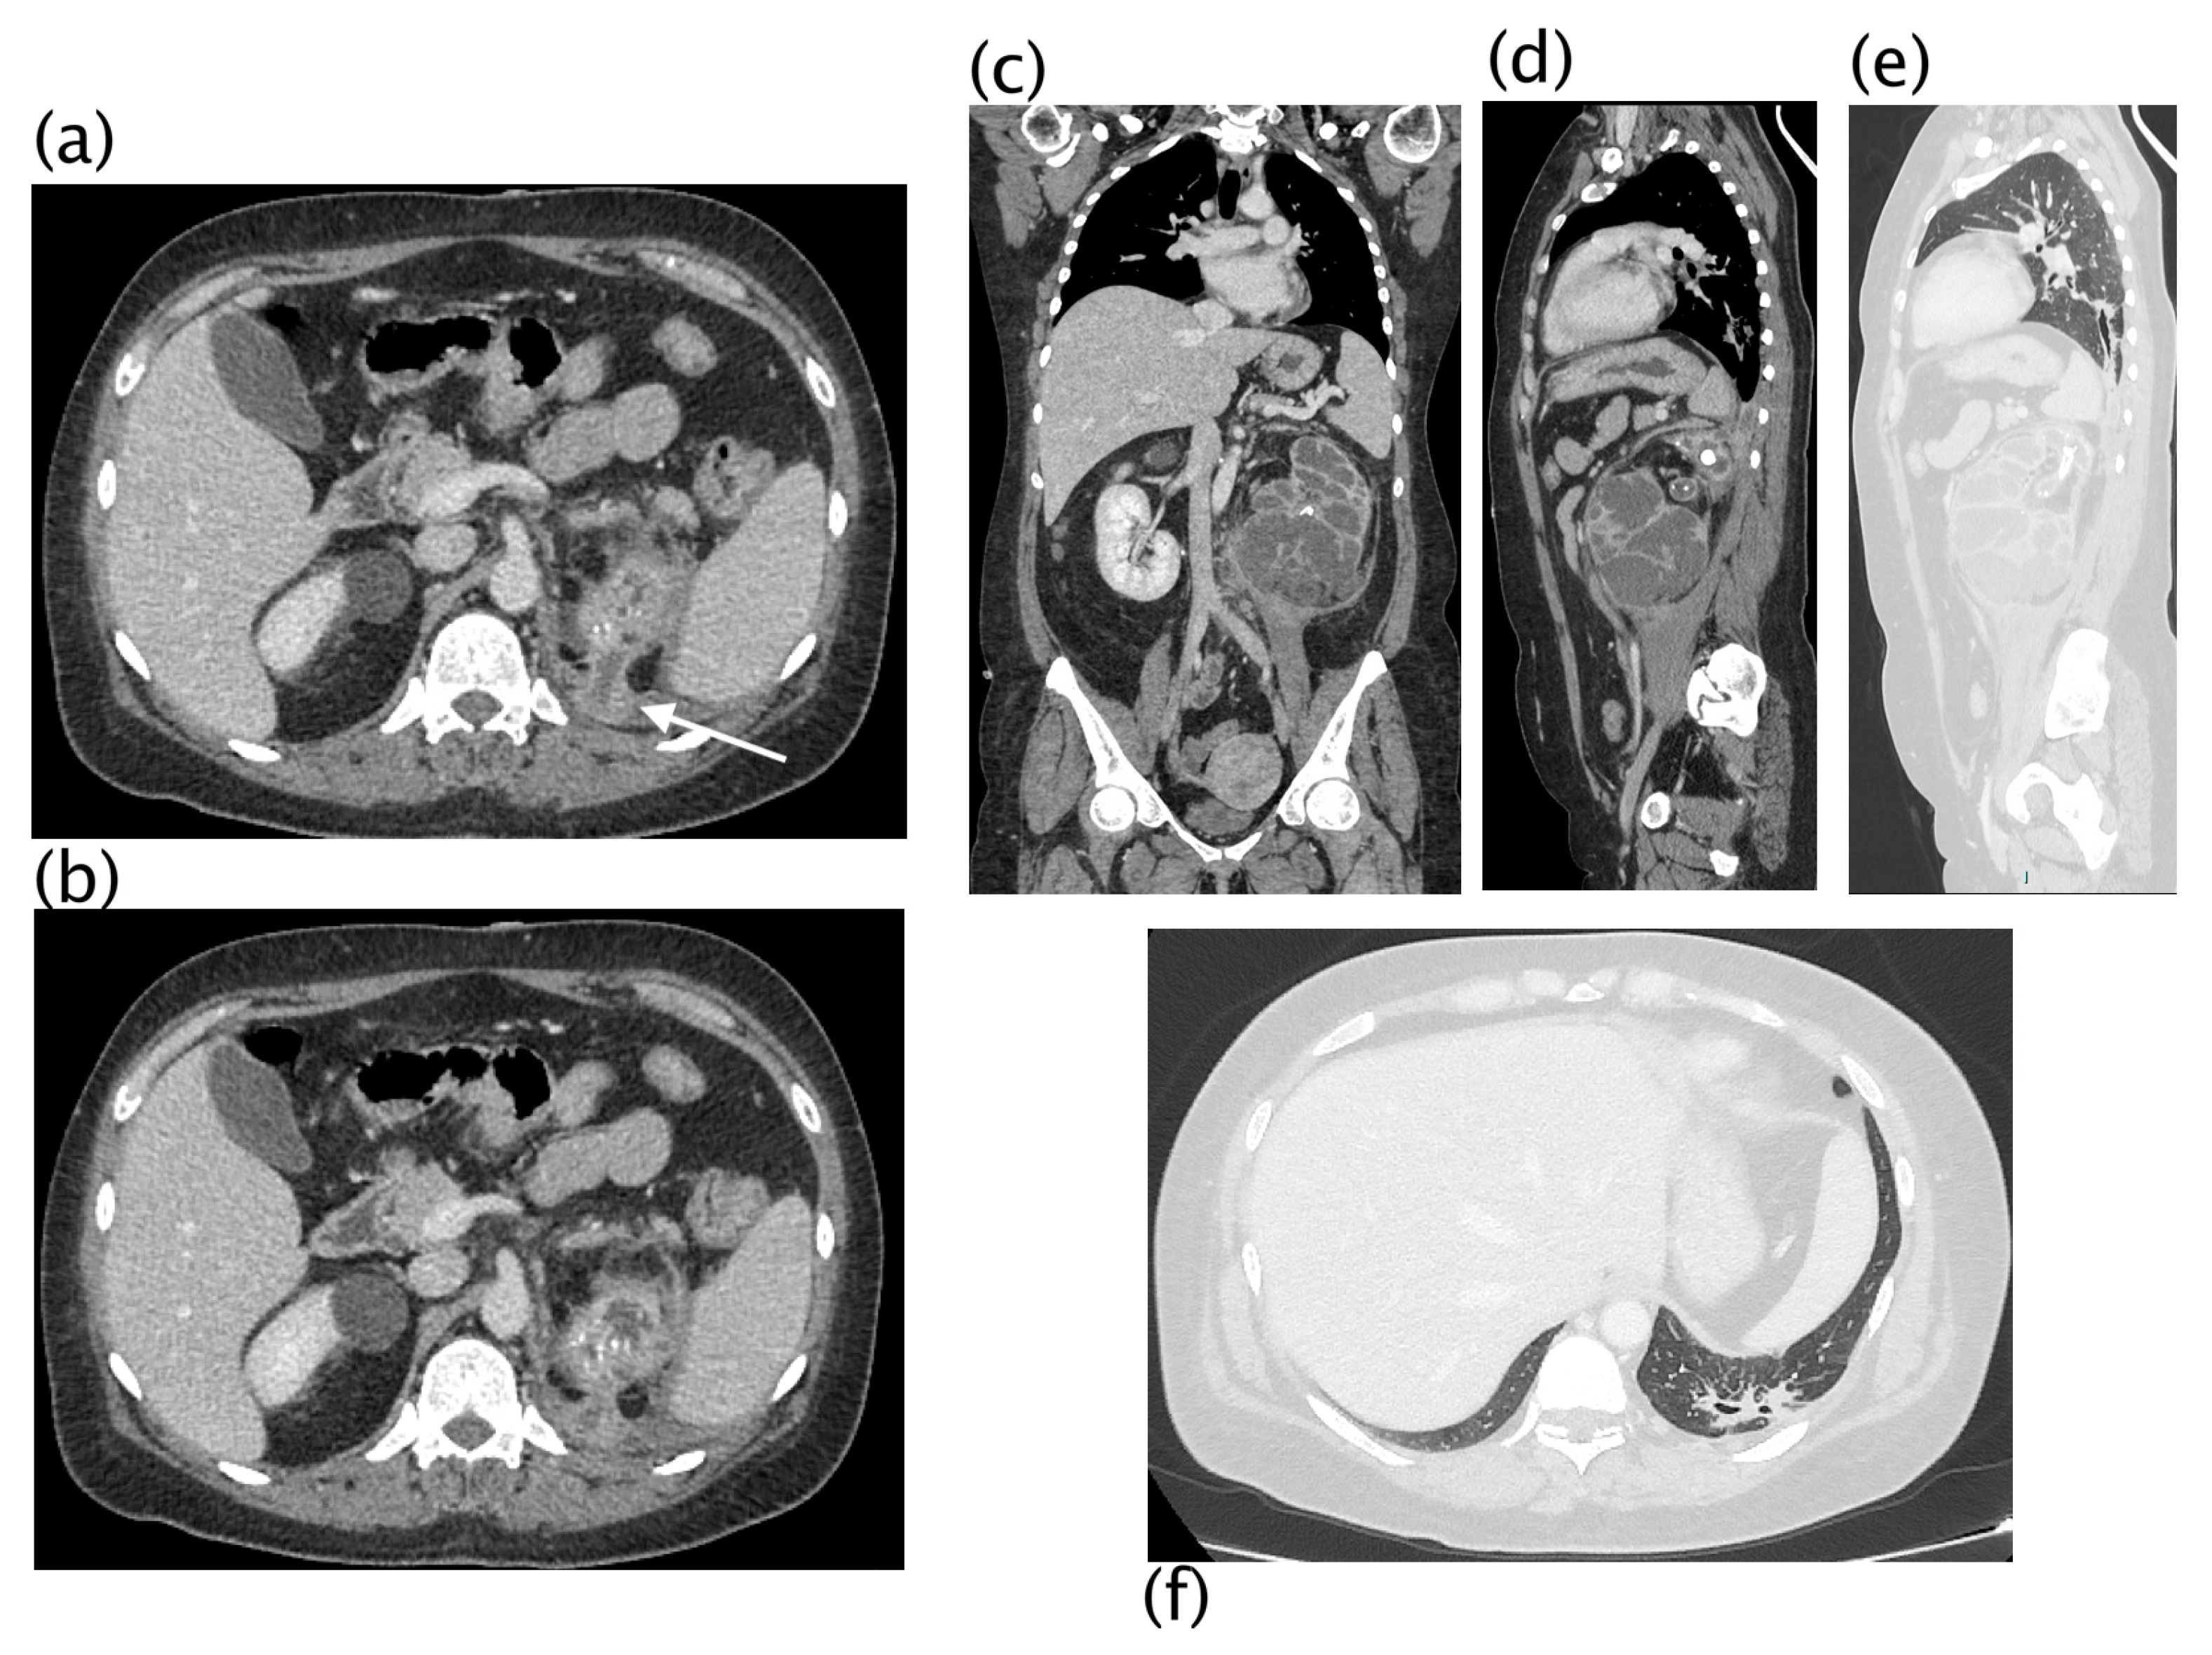

3. Results